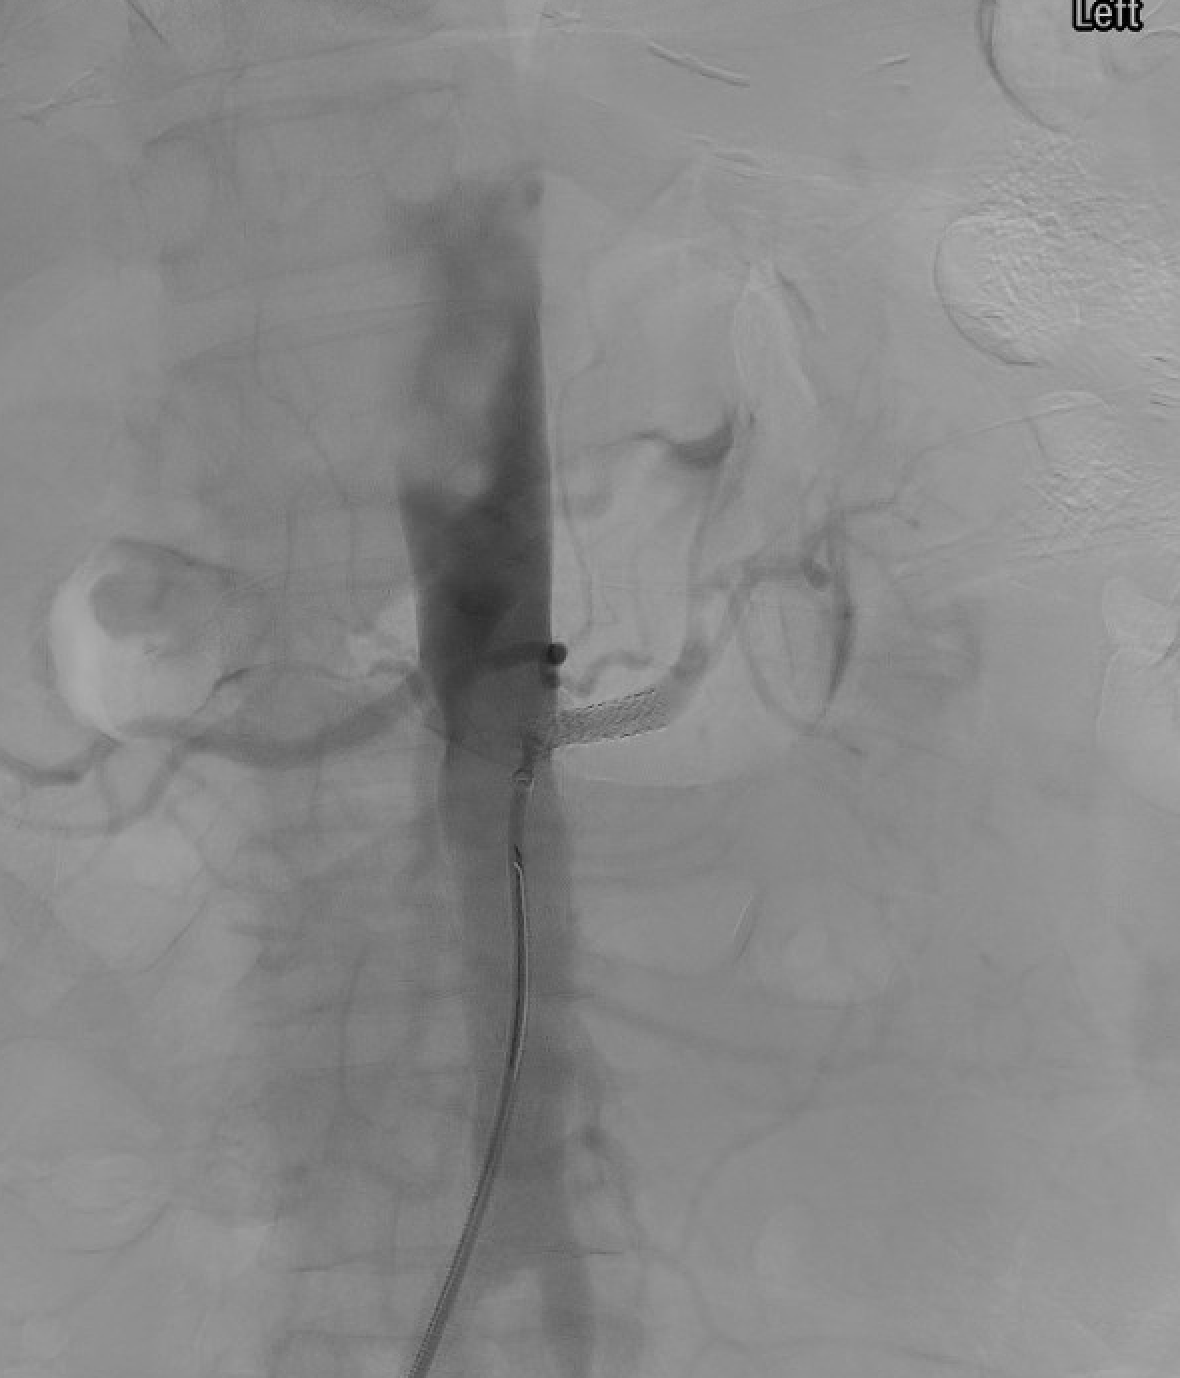

Left renal artery balloon angioplasty (PTA) — balloon inflated across the stenosis prior to stent deployment.Left renal artery stent placement — balloon-expandable stent deployed across the ostial stenosis with 1–2 mm protrusion into the aorta to ensure complete ostial coverage.

Primary stenting for atherosclerotic ostial RAS: balloon-expandable stent sized to reference vessel diameter (typically 5–7 mm); deploy with 1–2 mm protrusion into aorta to ensure ostial coverage; post-dilate to optimize apposition.

Primary PTA for FMD: high-pressure balloon sized 1:1 with reference vessel; multiple inflations; stent only for bailout (dissection, elastic recoil).